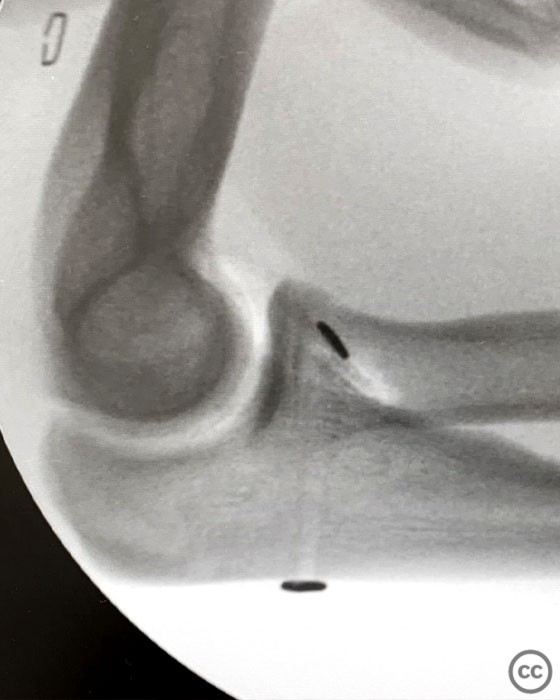

Anteromedial Facet and Sublime Tubercle...

Schleswig Holstein, Germany

Ulna - AO/OTA 2Ux

O'Driscoll type II coronoid fracture dis...

Endobutton fixation of an O’Driscoll ant...

Brussels, Belgium